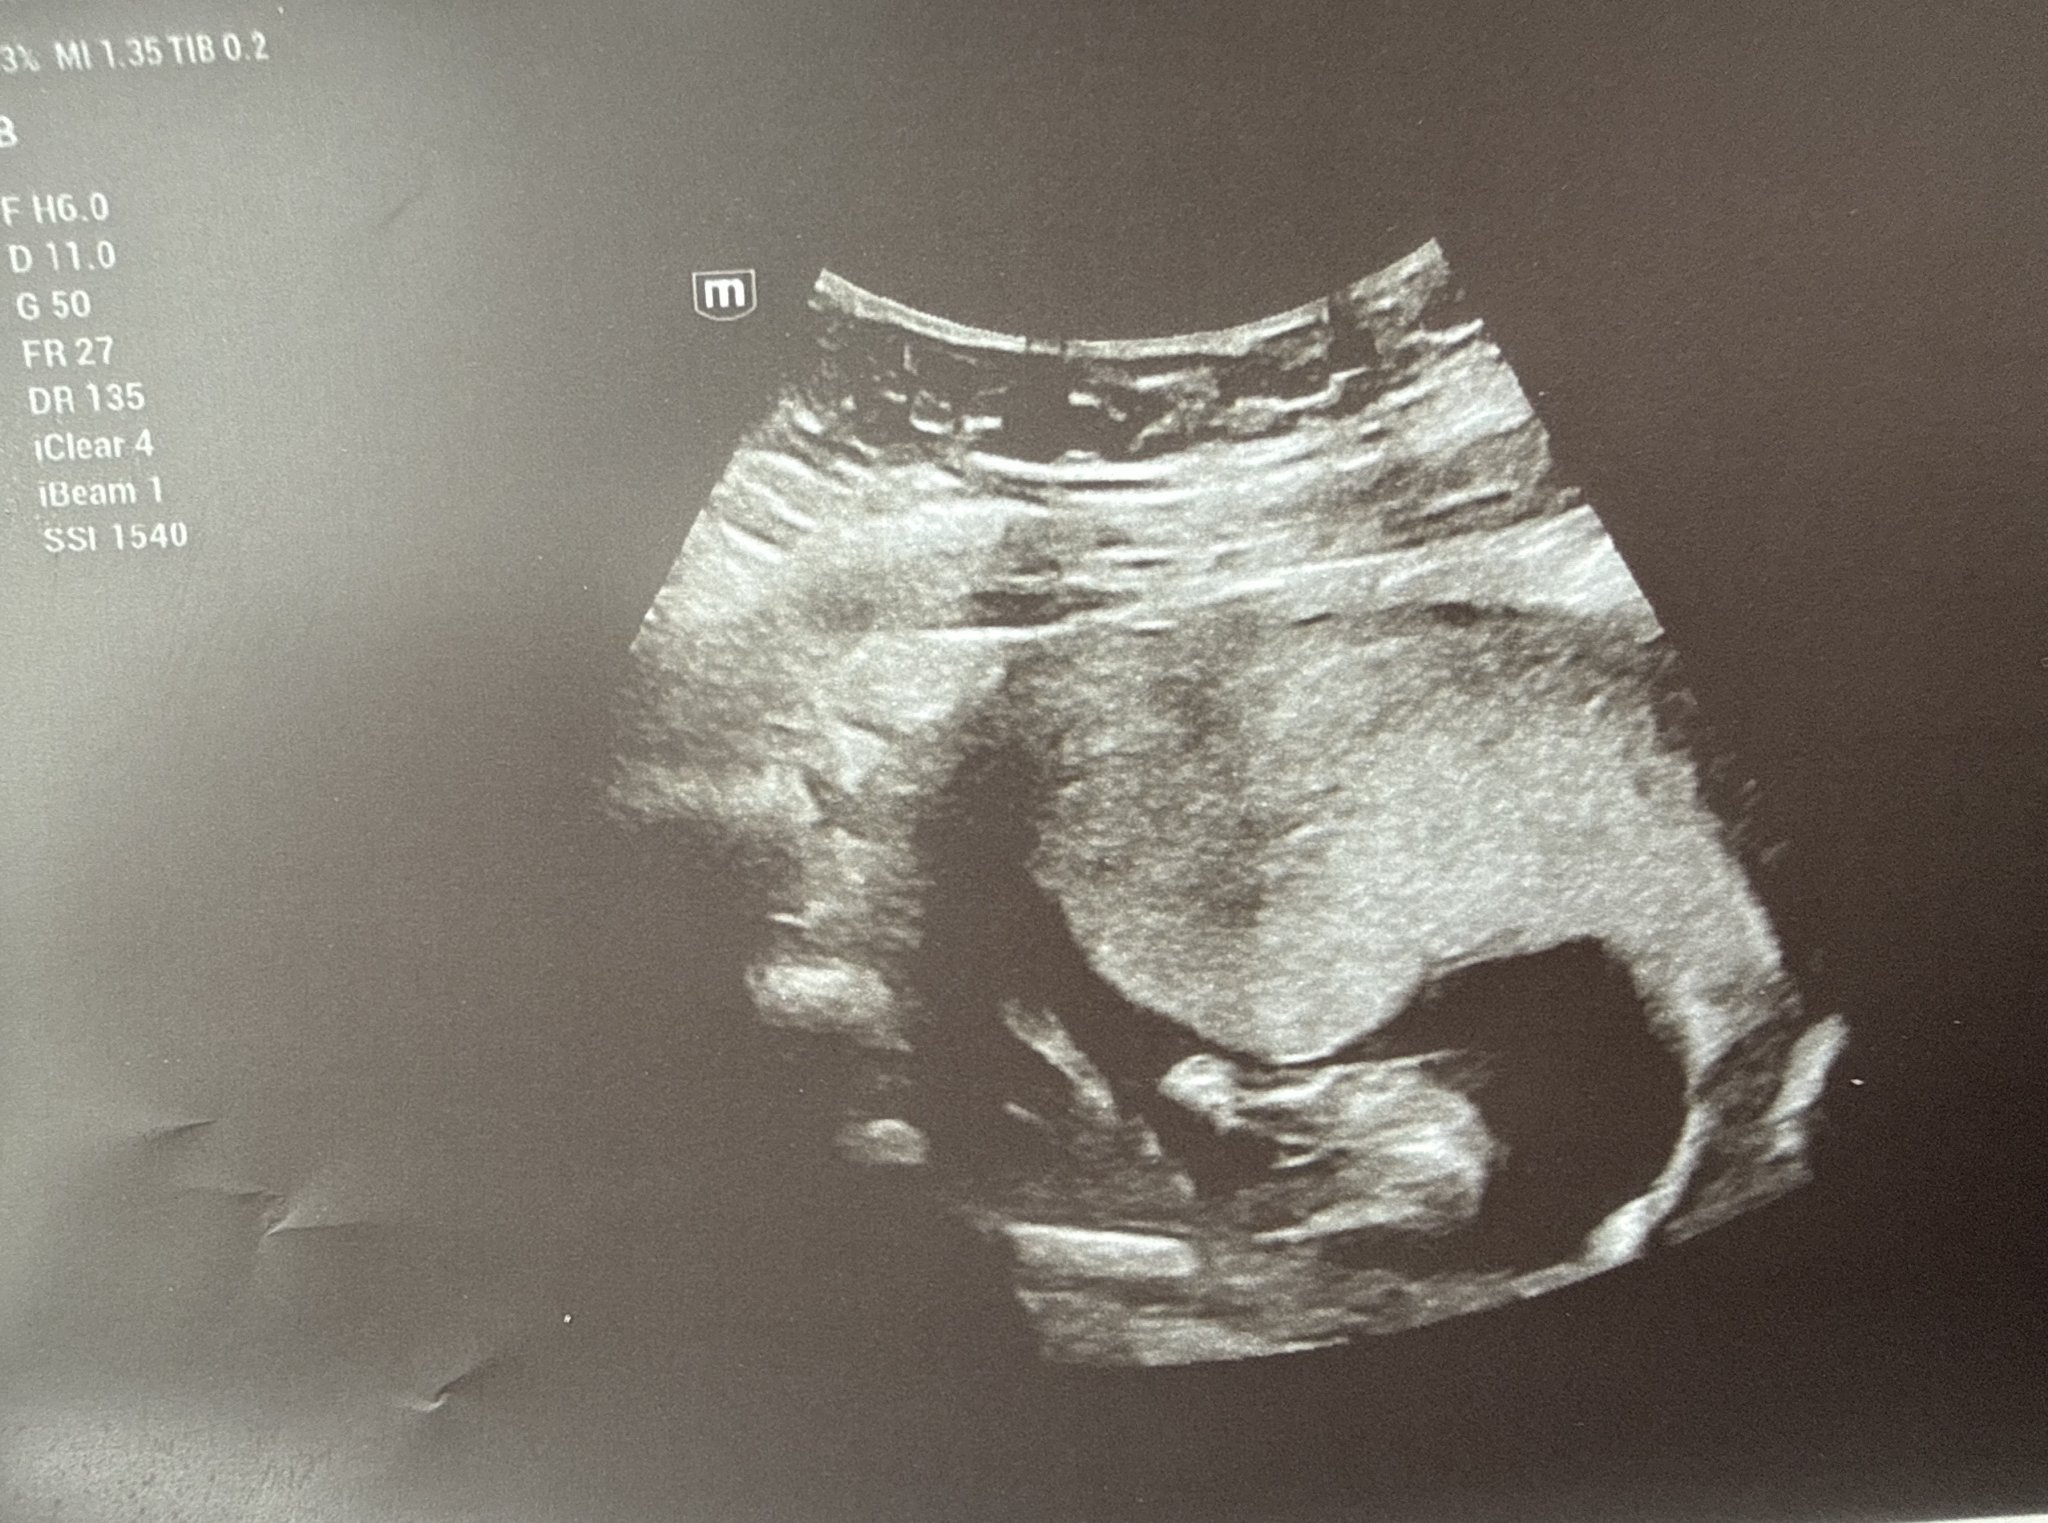

В 11г.с се видя,че бебчо е момче. Д-р Стратиева беше сигурна,не е било предположение,видяхме го и двете. И аз мисля,че е момче,съдейки по снимката.

В такава седмица половите органи не са развити, за това се дава предположение по “nub theory” - всички бебета имат генитален туберкул между крачетата в 11-13 седмица и според тази теория ъгъла между тази част и гръбначния стълб при момченцата е по-голям от 30 градуса, при момиченцата - по-малък от 30 градуса.

На мен също лекарката ми даде предположение по тази теория и позна пола.

Здравейте , лекарите имат предположения , но не на 100%. Какъв е пола на бебчето според вас ?

Според мен е момче.